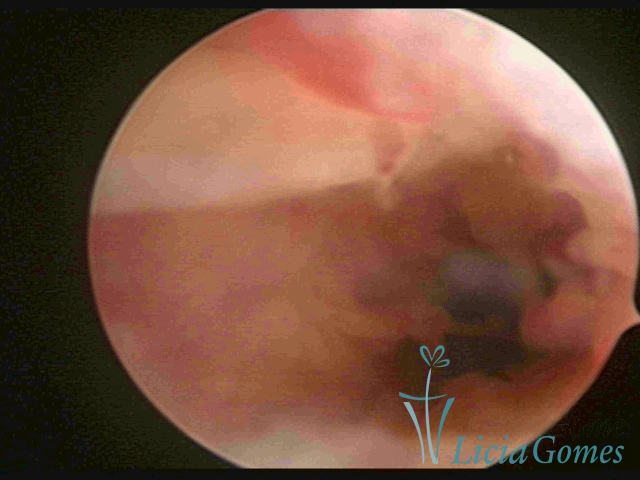

Uterine cavity with a fragmented IUD debris, inserted 46 years ago.